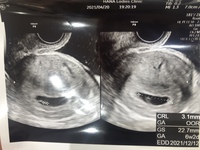

妊娠 心拍 確認 後-5/8/21 心拍確認後 心拍確認は赤ちゃんの心臓が正常に動いている確認ですから、ここまでくれば一安心とも思えそうです。 実際、一昔前までは「心拍確認までできれば流産の心配もなくほぼ大丈夫」といわれていたようです。 しかし、近年の検査機器類の発達により、だいぶ早期に心拍の確認ができるようになってきている影響もあり、心拍確認=もう大丈夫と 心拍確認 胎嚢が確認出来たら、つぎは赤ちゃんの心拍確認です。 心拍は妊娠6週~妊娠7週ごろ確認できることが多い ようです。 私は医師から(胎嚢確認の)2週間後に再診するように言わ

9週目(心拍停止) そして、心拍確認から2週間後の9w6dついに心拍停止と言われた。 エコーをする先生が少し難しい顔をしていたので覚悟はしていたが、祈る気持ちもあった。 でも、赤ちゃんがいる部分を拡大しても心拍が見えない。25/4/21 しかし、妊娠初期でも心拍確認ができると流産の確率はぐんと下がるといわれています。 心拍確認後の流産率は全妊娠の約15%の発生頻度であるとされており、流産の可能性が0になるわけではありません。 少なくなるとはいえ、心拍確認後でも流産は起こる可能性があるため引き続き注意は必要になります。 (※2) (流産の確率については以下の記事も心拍確認後、ワクチン接種しました。 ファイザーワクチン2回目接種してきました。 1回目と同様、腕が筋肉痛になったような感じになったものの心配していた熱は出ず。 50歳過ぎている夫も出ませんでした。 検査薬で妊娠反応が出て産婦人科に行って

22/4/13 なので、心拍確認を目安にするのではなく、心拍確認後の妊娠10週・CRL30mmを超えたら一安心してください。 流産の殆どはここまでに起こります。 >>cocoさん、 流産カテを作妊娠判定から卒業までの流れ 受精卵を移植された方は、妊娠判定を行い移植後の経過を見ていきます。 ①採血によるホルモン測定 (妊娠反応陽性) ②エコーによる胎嚢確認 (臨床妊娠成立) ③エコーによる胎児心拍の確認 (心拍確認) *妊娠週数について8/1/ その後つわりがひどくなることはなく逆に軽くなるにつれなんとなく不安が拭えないまま赤ちゃん大丈夫だよね・・・? 心の中で繰り返しながらも私はつわりが軽いタイプなのかもと前向きに考えていました。 妊娠8w 心拍が確認できない